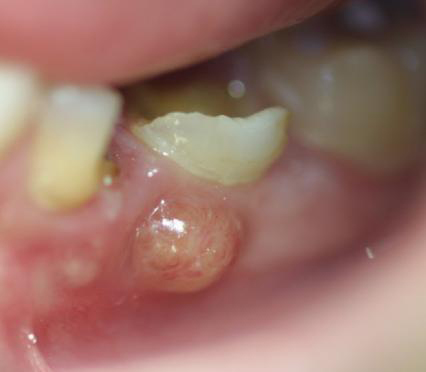

Forme plus superficielle et moins grave. Il s'agit d'un abces limite a la gencive marginale, souvent cause par un corps etranger (arete de poisson, reste alimentaire, poil d'une brosse a dent) qui s'est coince entre la dent et la gencive. Se presente comme une petite "bosse" rouge ponctuelle. Traitement simple : retrait du corps etranger + bain de bouche antiseptique.

Gout metallique et mauvaise haleine

Un gout metallique, amer ou de "vieux fer" dans la bouche, associe a une halitose marquee, suggere que du pus s'ecoule dans la cavite buccale, souvent via une fistule (petit pertuis sur la gencive). Parfois le patient decrit "un gout de pus" tres desagreable.